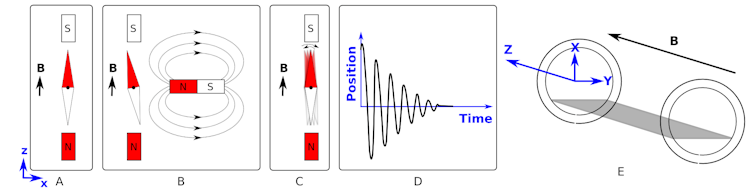

Figure A shows that a compass needle placed in a magnetic field aligns with the field. The direction of the field is indicated by the vector B in the diagram.

We can then “kick” (excite) the system by introducing a second magnetic field (figure B) and then subsequently removing it (figure C). This will cause the needle to rock back and forth like a pendulum until it returns to its rest position.

If we plotted the position of the red part of the needle relative to its start position, we would get something like the shape shown in figure D.

This shape of graph is called a damped sinusoidal wave. It is given this name as oscillates like a cosine (or sine) wave but its magnitude decreases (is damped) with time.

If, instead of removing the magnet entirely, we slide the second magnet back and forth (along the x-axis) at the correct frequency, we give the maximum “kick” to the needle and achieve a resonance.

Now, back to a practical discussion of MRI. Imagine a patient is laying in the scanner along the z-axis (see figure E) - the same direction as the strong magnetic field. We have already demonstrated what happens if the protons in the water in your body behaved like compass needles (see figure A) - they align with the magnetic field.